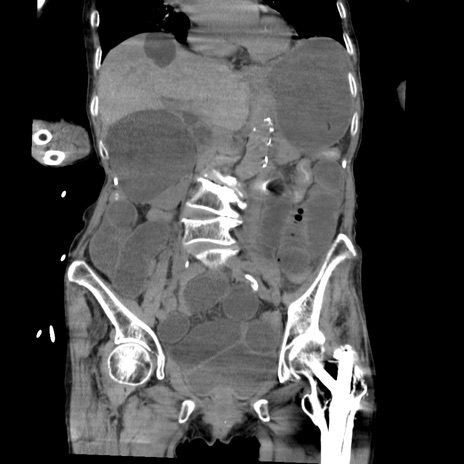

横断像

【症例】80歳代女性

【主訴】嘔吐、腹痛

【現病歴】数時間前より嘔吐あり。心窩部痛出現し、徐々に右下腹痛あり。その後も数回嘔吐あり救急搬送となる。

【既往歴】左大腿骨頚部骨折手術

【身体所見】腹部は膨隆しているが軟らかく圧痛なし。腸雑音はやや亢進。

【データ】WBC 12000、CRP 19.05